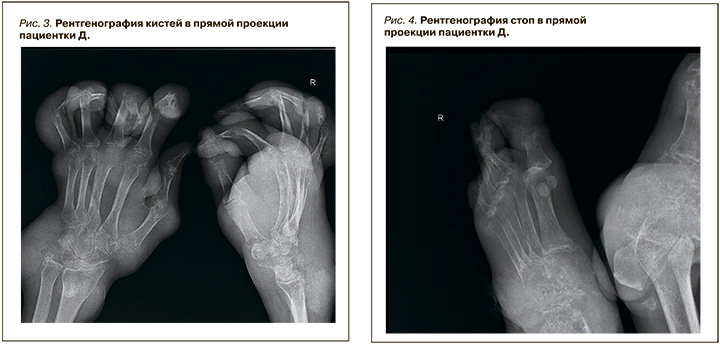

На рентгенограмме кистей (рис. 3) наблюдались выраженный диффузный остеопороз, сгибательные контрактуры, кистовидные просветления и краевые узуры, подвывихи.

Данные рентгенограммы стоп: диффузный остеопороз, сужение суставных щелей, кистовидные просветления в костях, краевые узуры, вывихи и подвывихи в межфаланговых суставах (рис. 4).